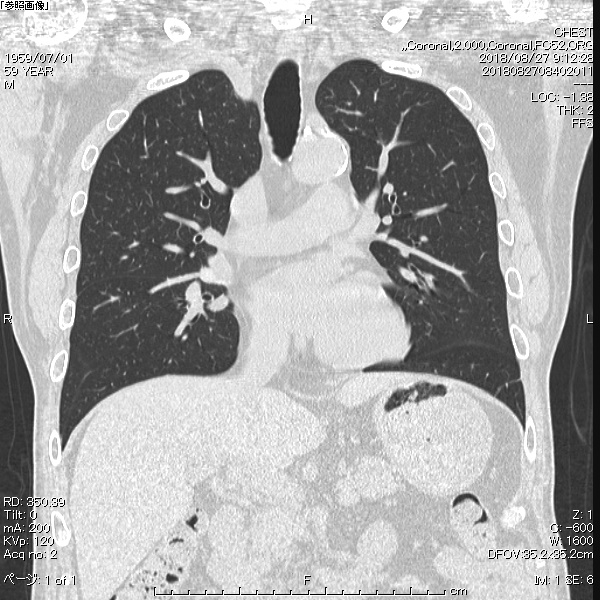

マルチスライスCT撮影装置

Supria

当院では64列マルチスライスCTを導入しています。

高速スキャンが可能で、一回の息止めで広範囲の撮影が可能です。

画像処理ソフトも使用し、

鮮明な3D画像や様々な角度からの断層画像を診断に役立てています。

また患者様の体に応じて、管電流を自動調整することにより、被ばく線量を抑えることが可能です。